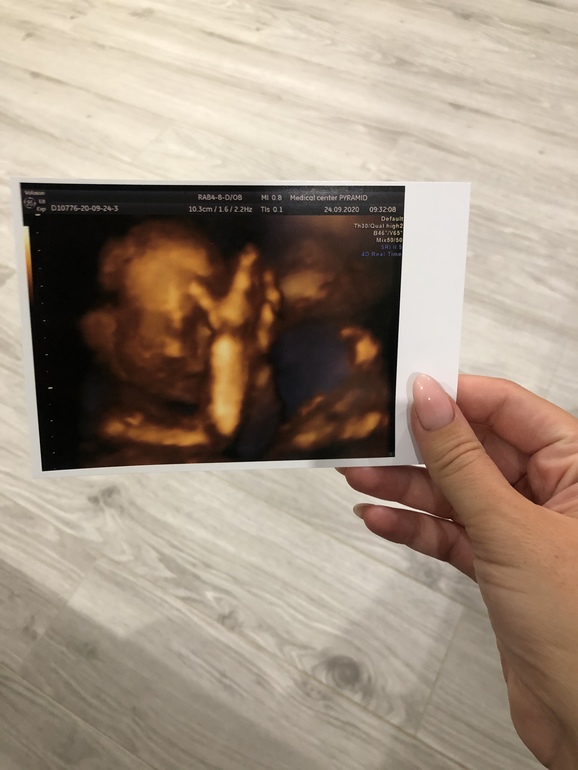

Сегодня ходили на 2 скрининг, маленько остаём от своего срока, до этого опережали, сейчас на пару дней остаем 😀 вес 281 гр, все органы развиты в срок и без Патологий. Такая она у нас стесняшка, ни в какую не даёт посмотреть на ее личико 🥰🎀 Муж так умилялся сегодня на узи, говорит моя кнопочка, копия моей любимой мармеладки(он меня так называет)😍 Он уверен, что она похожа будет на меня ♥️

И наш цветочек, Сомнений больше нет, что девочка у нас 🎀